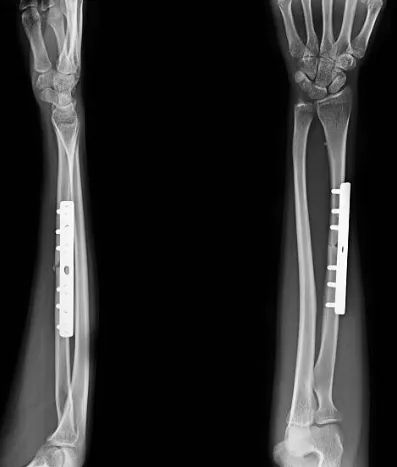

開放性復位內固定手術:在麻醉下,切開皮膚,通過手術器械將骨頭復位並使用螺釘、鋼板、釘子等固定器材將骨頭固定在正確的位置。

開放性復位外固定手術:使用鋼釘或針對骨骼的外固定器件,將骨頭復位並固定。